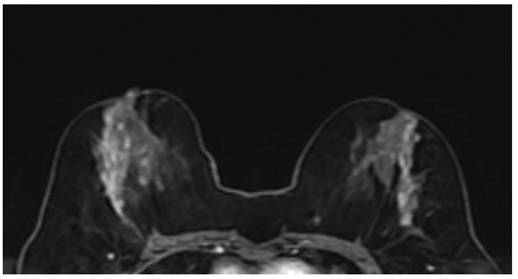

Figure 2

Contrast enhanced breast MRI, focal heterogeneous enhancing NME lesion (a), biopsy result of DCIS in a 45-year-old patient. Second image (b), 52 years old, focal clustered-ring enhancing NME lesion, invasive carcinoma as a result of biopsy.

The contrast enhancement characteristics of patients with NME lesions detected on MR imaging are summarized in Table 3. Among the contrast distribution characteristics of NME breast lesions, there was a statistically significant difference between benign and malignant lesions in those showing linear, segmental, and regional distribution (P<0.05). Segmental distribution was higher in malignant NME lesions (35/118, 29.7%) than in segmental distribution in benign lesions (71/342, 20.8%). While 82 (24%) of benign NME lesions showed linear distribution, 41 (34.7%) of malignant lesions showed linear distribution. In those showing regional distribution, the proportion of malignant lesions (8/118, 6.8%) was found to be benign while the proportion of lesions (56/342, 16.4%) was found to be benign. Among internal enhancement patterns, the frequency of clustered-ring enhancement was statistically significantly higher in malignancies (20/118, 16.9%) than in benign lesions (33/342, 9.6%) (P<0.05). In those with heterogeneous internal enhancement patterns, benign NME lesions (182/342, 53.2%) were more common than malignant lesions (47/118, 39.8%). The difference between benign and malignant NME lesions for persistent type (type I) and wash-out type curve (type III) from dynamic enhancement curves was statistically significant (P<0.05) (Figure 2 and 3). The wash-out type curve (type III) was more common in malignancy (63/118, 53.4%) and higher than in the benign group (109/342, 31.9%). The incidence of type I was higher in benign lesions (99/342, 28.9%) than in malignant lesions (8/118, 6.8%) (P=0.001). The sensitivity and specificity of the kinetic curve model in predicting malignant NME lesions were 93.2% and 71.1%. In terms of diffusion restriction, diffusion restriction was observed in 94 (79.7%) of malignant lesions, while diffusion restriction was observed in 244 (71.3%) of benign lesions, which was not statistically significant (P=0.178) (Table 3).

The MRI features of malignant lesions were further analysed and the results are shown in Table 4. The MRI features of DCIS and invasive cancer were compared with benign lesions. Among the distribution features and internal enhancement patterns, linear, segmental, regional distribution, and clustered-ring enhancement can help distinguish between benign and malignant NME lesions (Figure 4). However, there was no statistical difference in the distribution features between invasive carcinoma and carcinoma in situ. Interestingly, in terms of internal enhancement patterns, the rates of heterogeneous enhancement for invasive carcinoma (4/28, 14.3%) were found to be statistically significantly lower than those for DCIS lesions (43/90, 47.8%) (P<0.05). The rates of clumped and clustered-ring enhancement were found to be higher in invasive carcinoma (11/28, 39.3% and 9/28, 32.1%, respectively) than in DCIS lesions (21/90, 23.3% and 11/90, 12.2%, respectively) (P<0.05). According to dynamic curves, benign lesions were more likely to show type I features in both groups (P=0.001, 0.009). The wash-out curve (type III) was higher in both invasive cancer (14/28, 75%) and DCIS (49/90, 54.4%) than in benign lesions (109/342, 31.9%) (P<0.05). Twenty-three (82.1%) of invasive cancers showed diffusion restriction, while 244 (71.3%) of benign lesions showed diffusion restriction. The difference was statistically significant (P<0.05). However, there was no significant difference in diffusion restriction between DCIS and benign lesions.